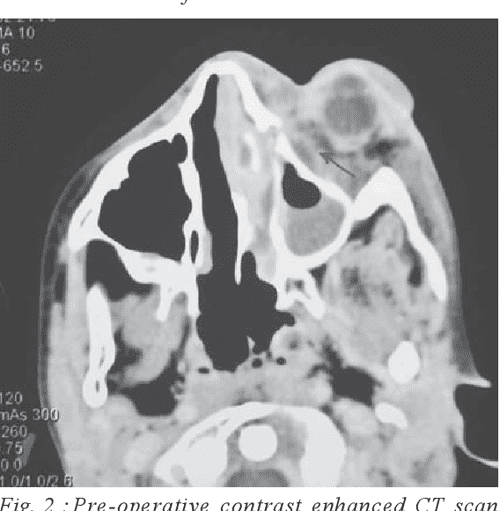

CT scan (axial plane) revealed subperiosteal abscess and lateral sinus Subperiosteal Abscess Dental Radiology This study clearly defines that. Gaining knowledge of which imaging protocol to use, the relevant anatomy of the teeth and related structures, and the key imaging findings of dental emergencies will help radiologists identify infections, trauma, and complications of dental procedures. Orbital abscess secondary to an odontogenic cause is a rare, but dangerous. Dental periapical inflammation is common and can. Subperiosteal Abscess Dental Radiology.